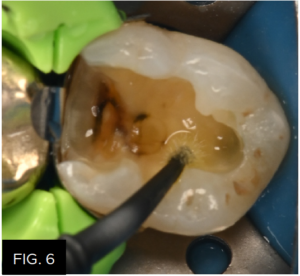

The new Scotchbond™ Universal Plus Adhesive (3M) is then scrubbed into the enamel and dentin for 20 seconds. This newer version is similar to Scotchbond™ Universal but now has an incorporated dual-cure activator, is radiopaque, and can be used to bond to caries-affected dentin. As a universal adhesive, Scotchbond™ Universal Plus Adhesive could have been used in the selective-etch mode while still maximizing the enamel bond strengths, or the self-etch mode. This universal adhesive is designed to be used in one application due to its thicker viscosity, and scrubbing the adhesive will drive it onto the dentin surface and into the dentinal tubules for optimal bond strengths and prevention of post-op sensitivity. Once this is thinned and the ethanol solvent is evaporated (approx. 5 sec), the adhesive is light cured for 10 seconds. (FIG. 6)